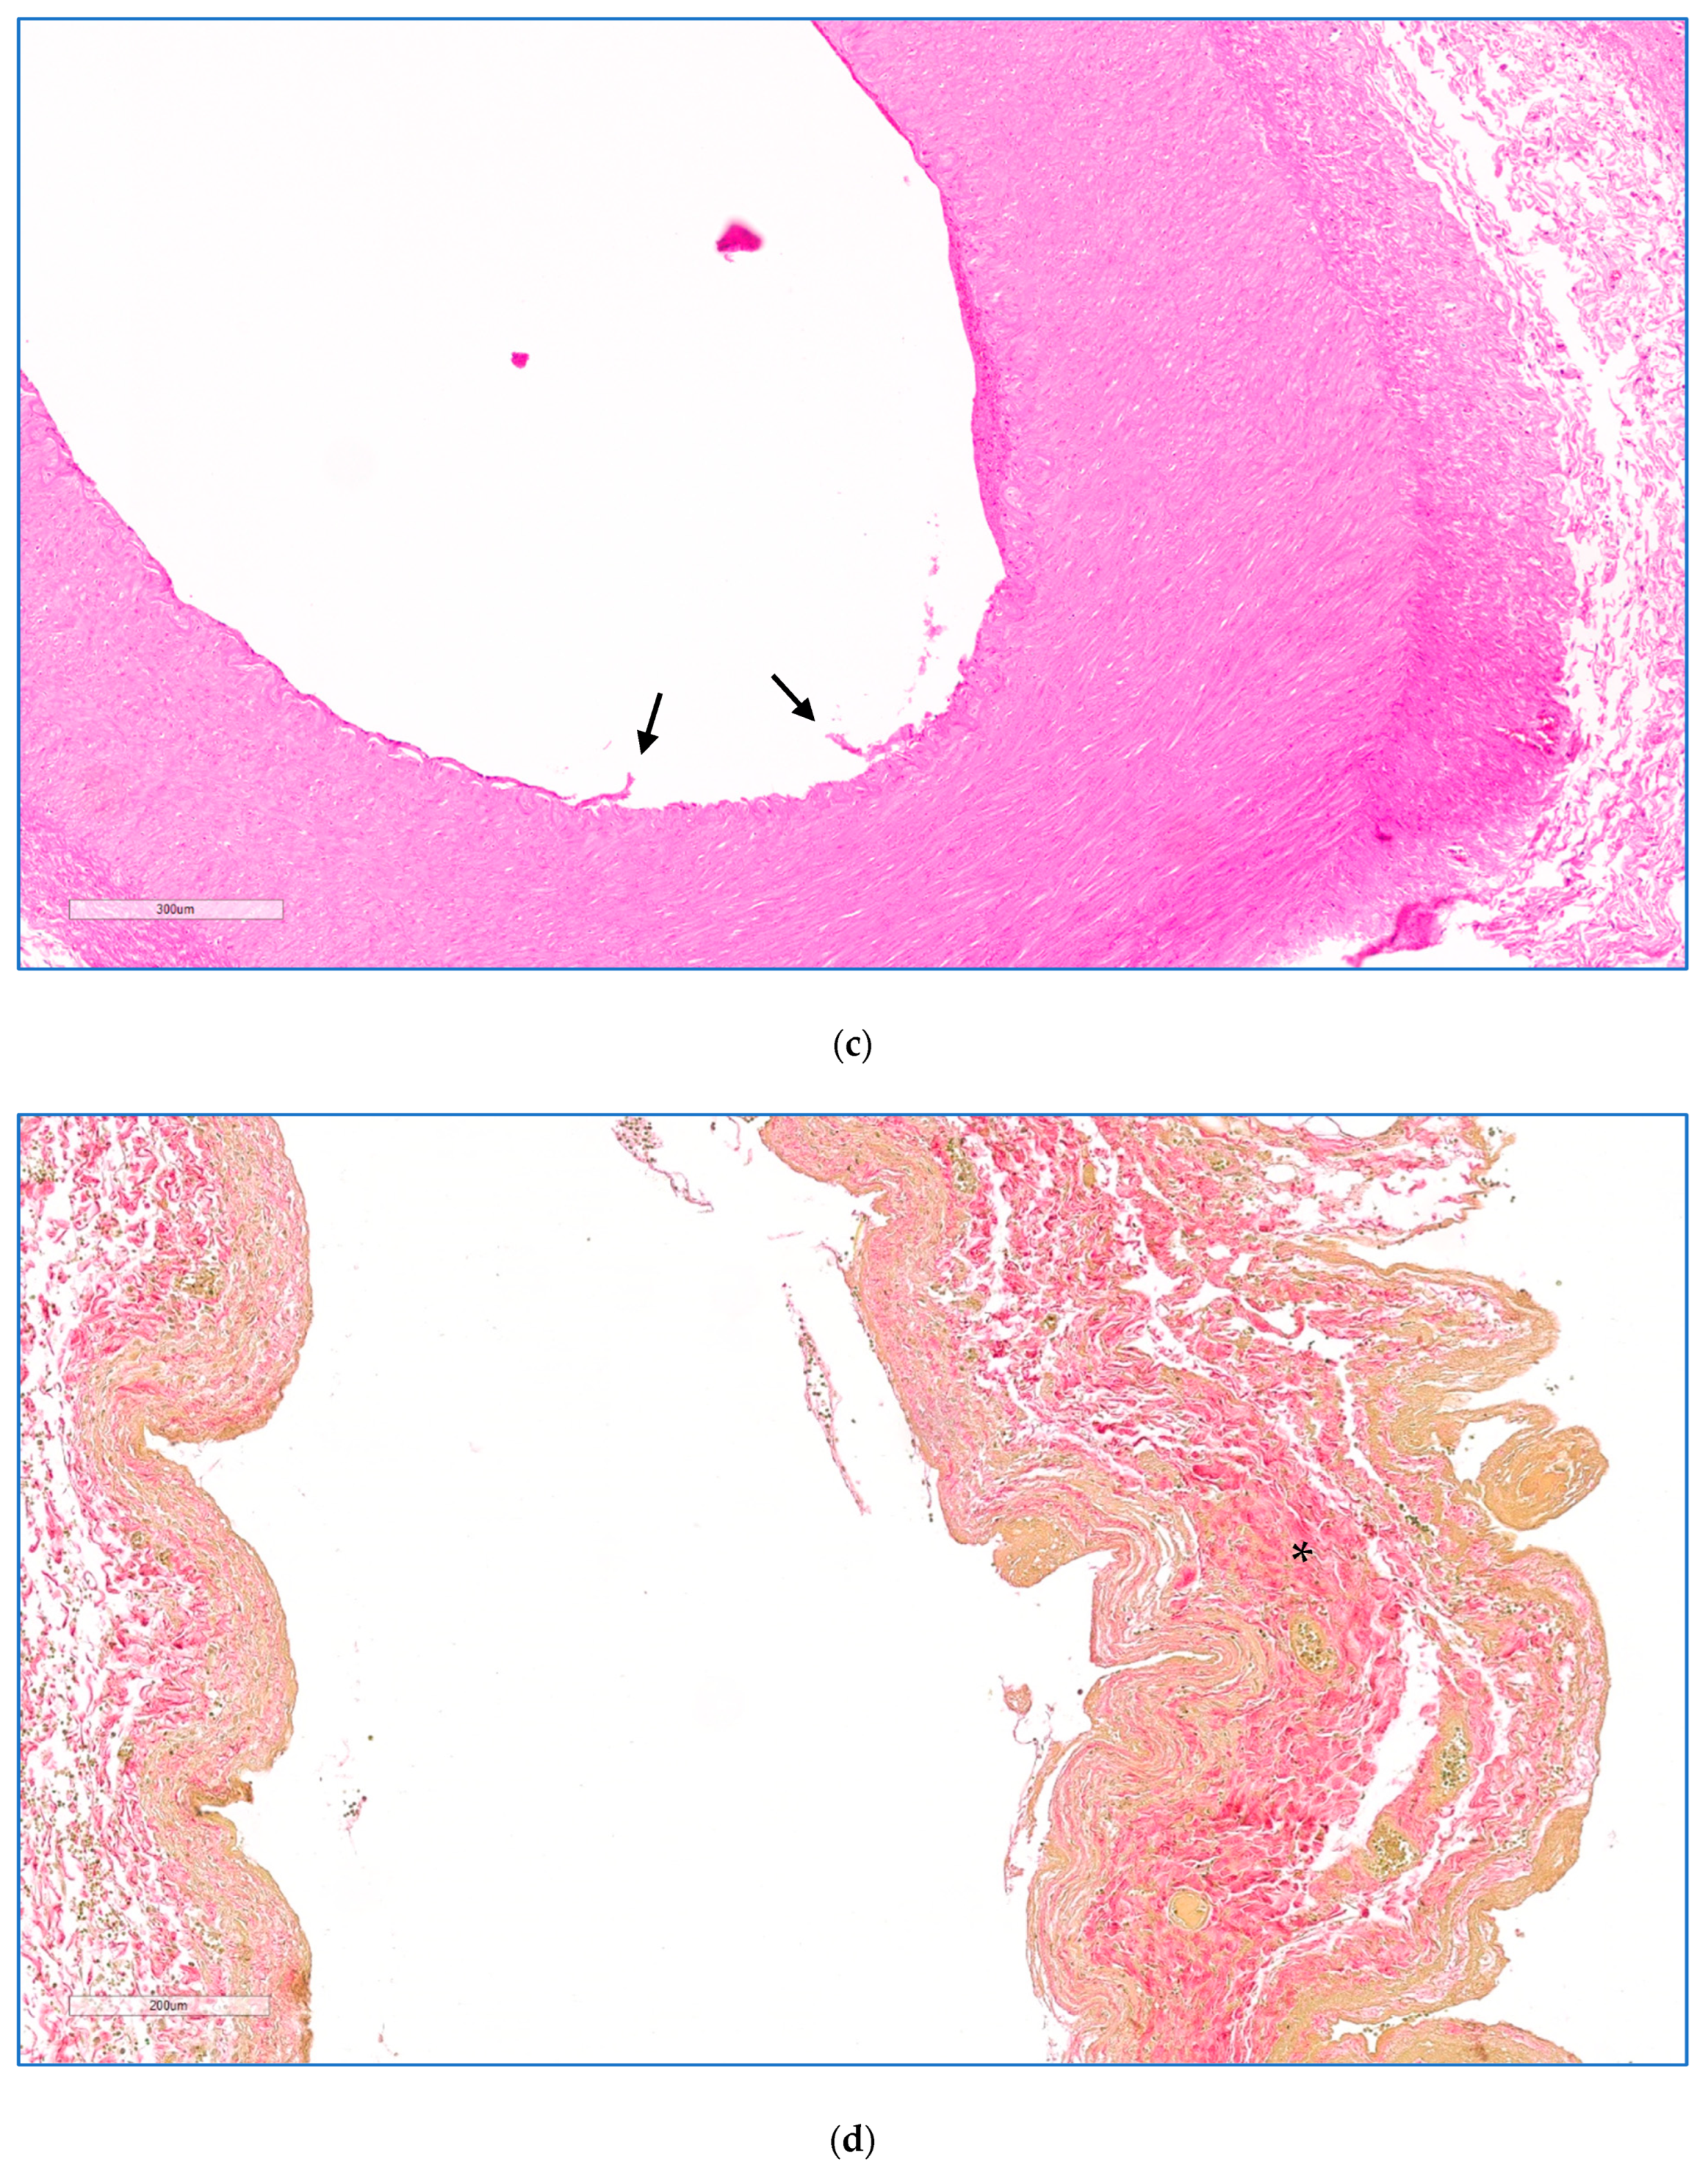

On microscopic examination, areas of coagulative necrosis were seen in the pancreas of all animals, except animal 3. These were often patchy and sometimes more extensive, particularly in the animals that had received the higher drug doses. An overview of the entire treated area of animal 5 treated at a dose of 0.8 mg·kg−1 is shown in Figure 4a. The distance in mm between the outer edge of the treated vessel and the zones of necrosis in the tissue from each animal was measured (Table 1). At high magnification, the interface between necrotic and morphologically viable tissue was identified as a distinct line (Figure 4b). No definite evidence of necrosis was seen in the pancreas of animal 3, treated at the lowest drug dose.

Figure 4.

(a) Histology of animal 5 treated at a dose of 1.6 mg·kg−1. Showing an H&E image with a low-magnification overview (3 mm scale) encompassing the treated splenic vein, splenic artery, a necrotic margin of perivascular necrosis extending into the pancreas, and a sharply demarcated necrotic zone boundary (dotted line), beyond which the pancreatic parenchyma is normal. The perivascular necrotic zone was characterised as having patchy necrosis of pancreatic lobules, with associated cytosteatonecrosis extending into the septa, microthrombosis, haemorrhage, and abundant inflammation rich in neutrophils and macrophages. Higher magnifications of the artery, vein, and pancreas are shown in (b–d). (b). High power image of pancreas showing sharp demarcation (dotted line) between necrotic pancreatic tissues on the left (resulting from EPA) and viable pancreas on the right (H&E, scale 200 μm). (c) High power image of the splenic artery (animal 2) showing severe, extensive necrosis of the endothelial lining, endothelial cell detachment (arrow), endothelial cell degenerative change, and marked degeneration of the deep layers. (HE, scale 200 μm). (d) High power image of a treated splenic vein, showing collagenisation of the wall (*), with atrophy of the muscular media, and mild transmural inflammatory infiltrate associated with focal ulceration of the endothelium (EVG, scale 200 μm).